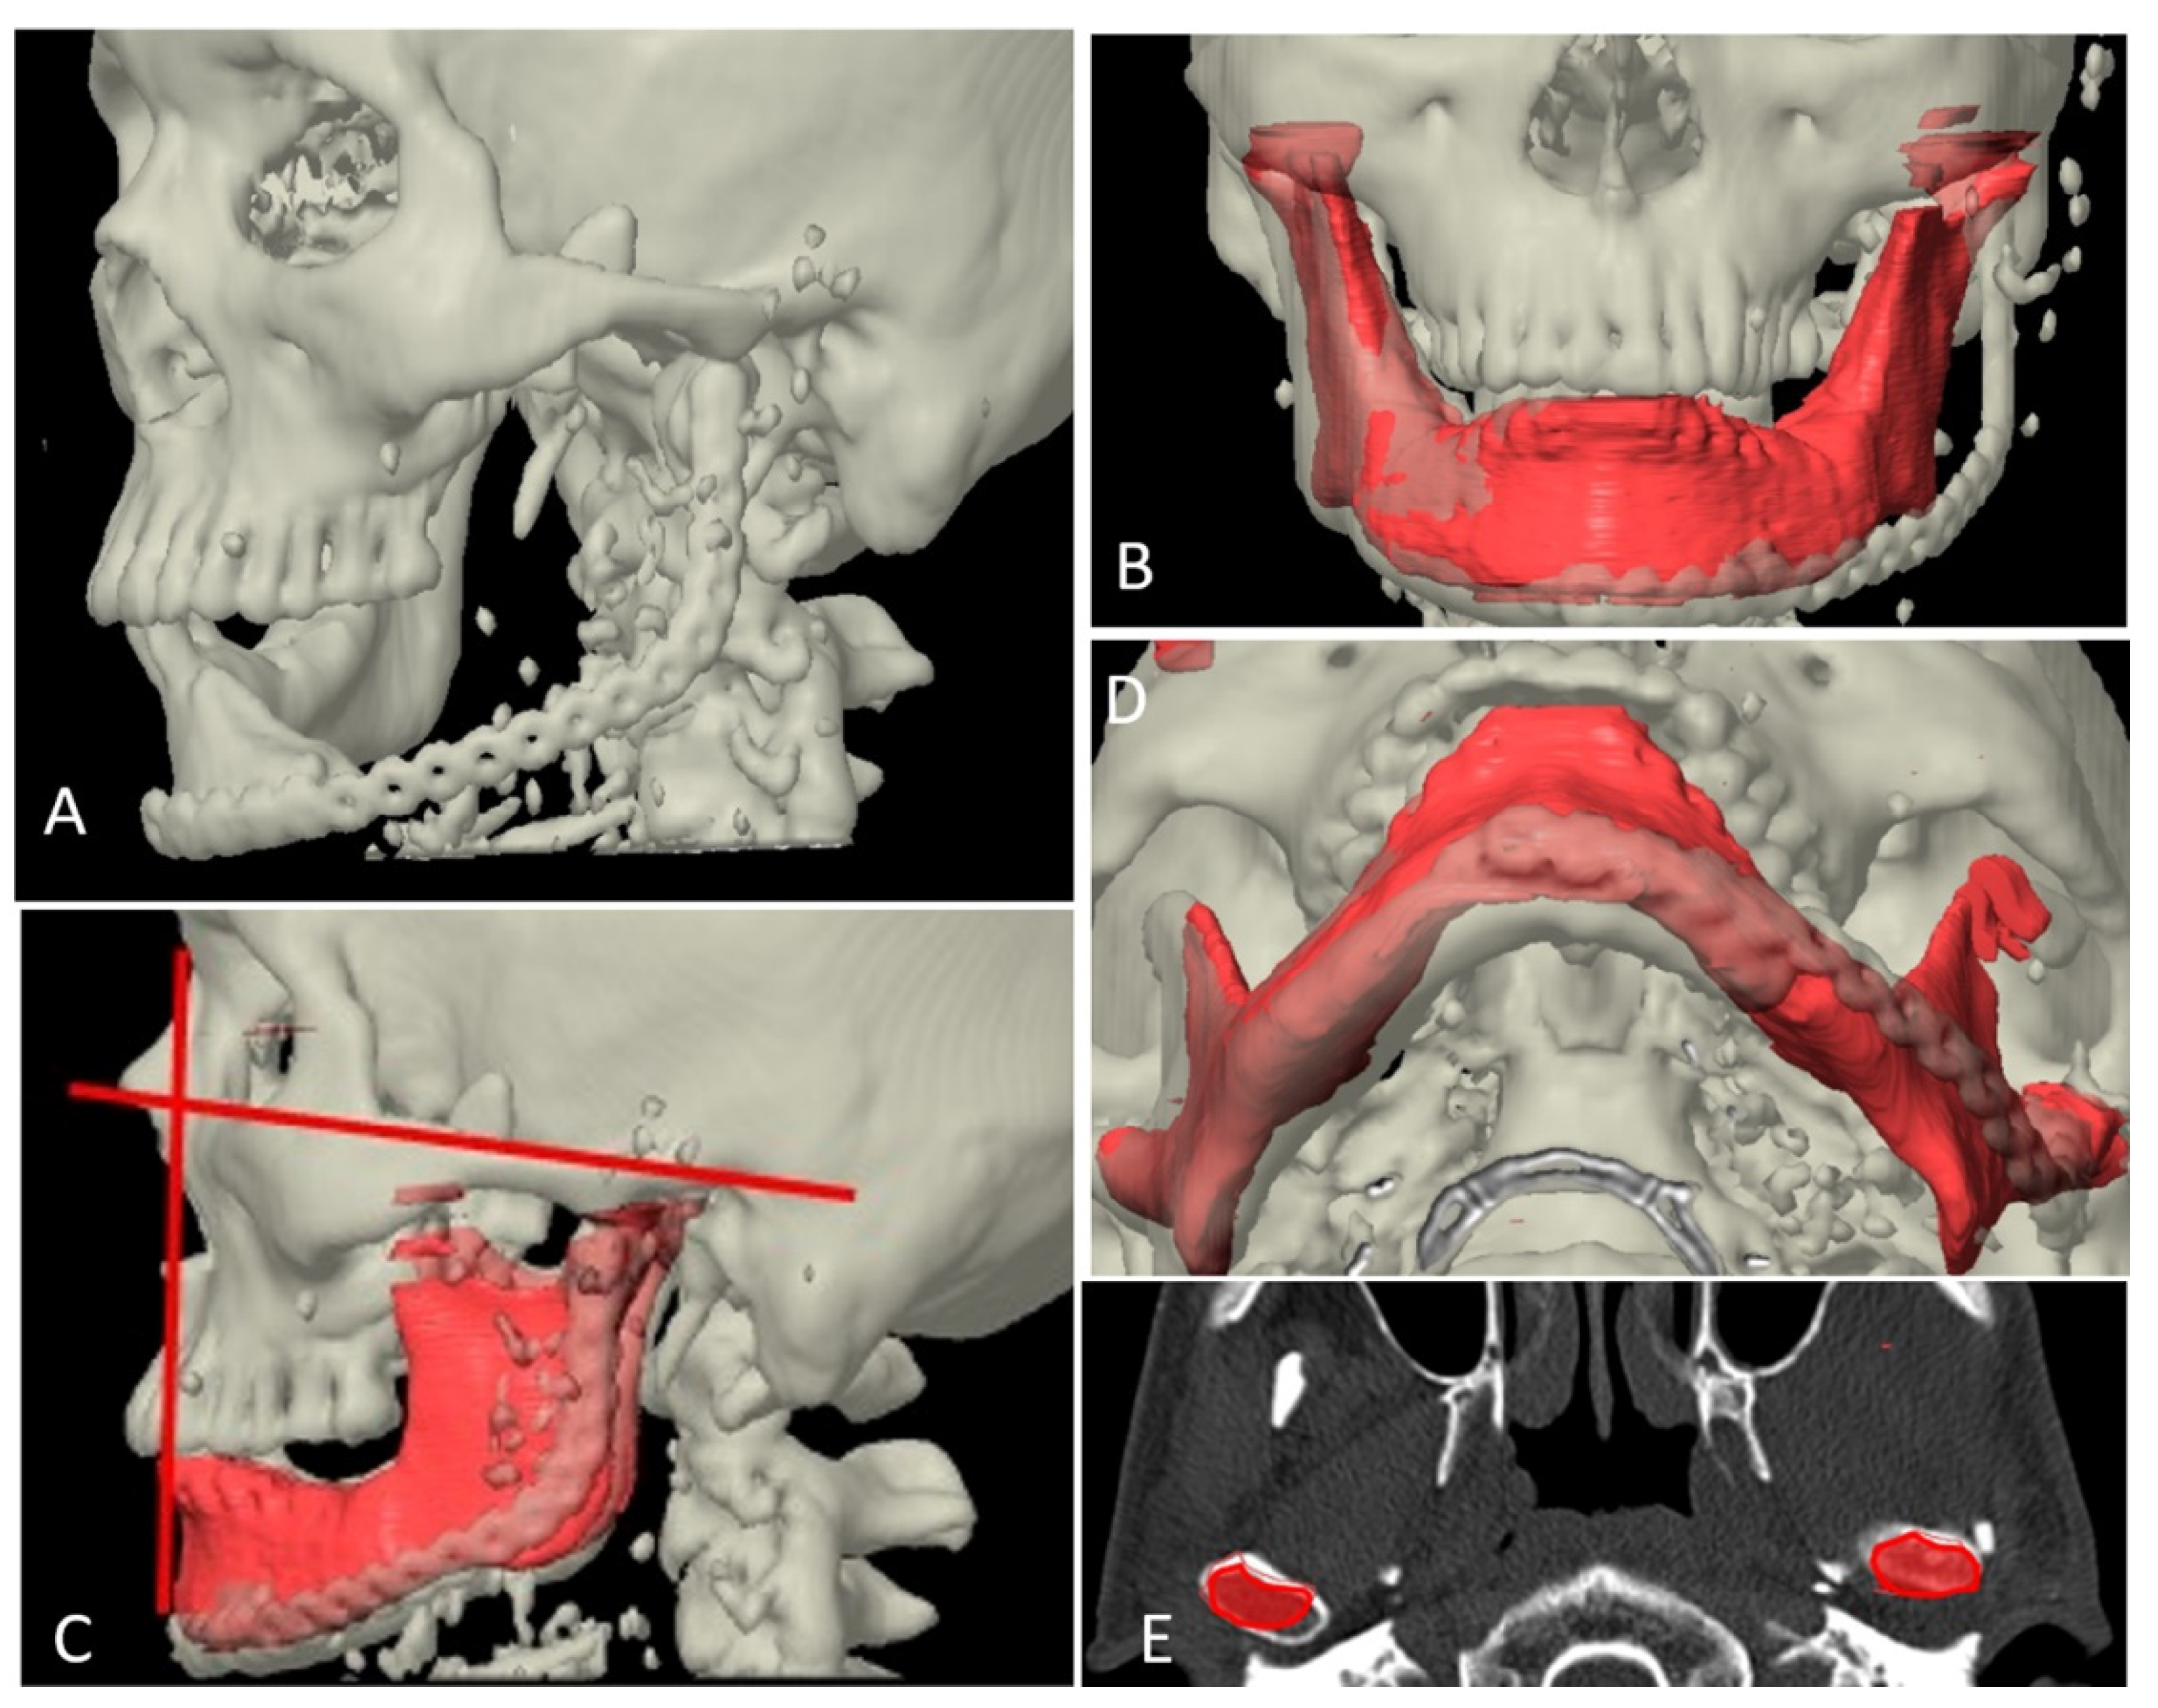

Figure 8.

Superimposition of planned and postoperative image in category I. (A) 3-dimensional view of outcome after reconstruction. (B) Superimposition of virtual plan (orange color) and post-operative data. (C) Axial view showing good match of reconstructed fibula to simulated mandible. (D) Sagittal view showing good match of reconstructed fibula to simulated mandible.

Figure 9.

Superimposition of planned and postoperative image in category II. (A) 3-dimensional view of outcome after reconstruction. (B) Superimposition of virtual plan (purple color) and post-operative data. (C,D) Axial view showing good match of reconstructed fibula to simulated mandible.

Figure 10.

Superimposition of planned and postoperative image in category III. (A) 3-dimensional view of outcome after reconstruction. (B) Superimposition of virtual plan (red color) and post-operative data. (C) Axial view showing matching of reconstructed fibula to simulated mandible. (D) Sagittal view showing matching of reconstructed fibula to simulated mandible.